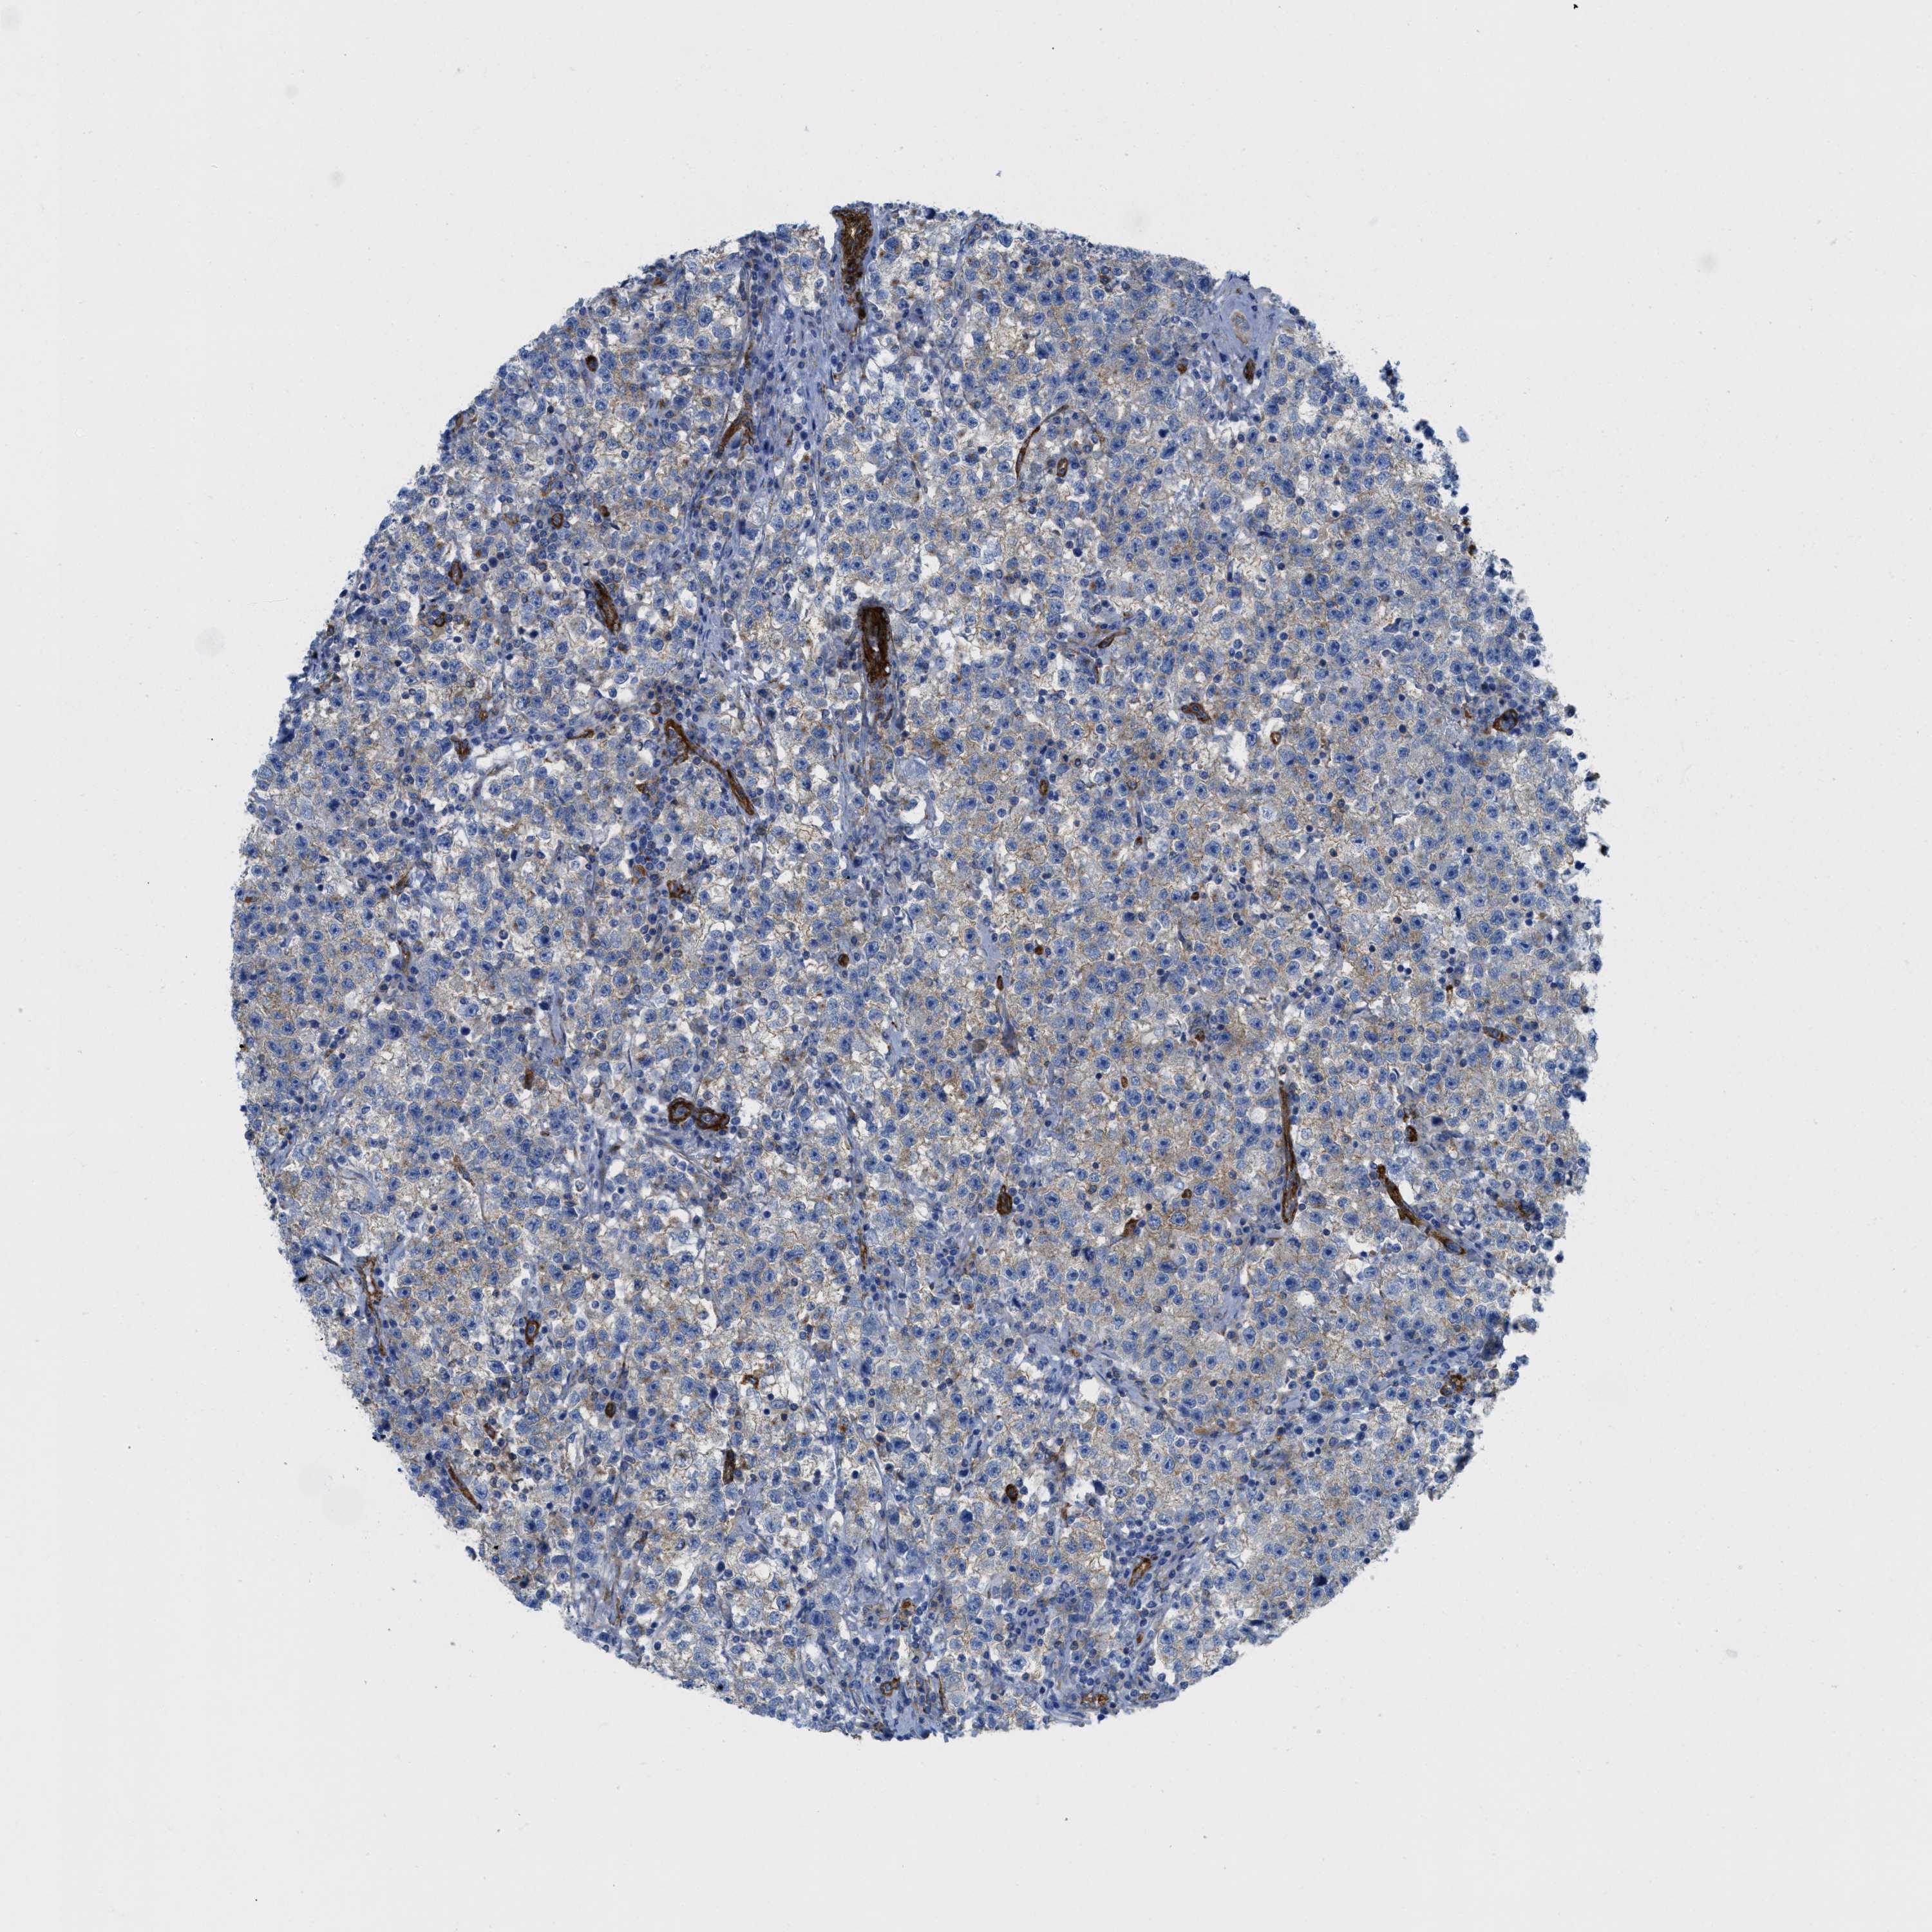

TESTIS CANCER - Protein expressioni

A mouse-over function shows sample information and annotation data. Click on an image to view it in a full screen mode. Samples can be filtered based on level of antibody staining by selecting one or several of the following categories: high, medium, low and not detected. The assay and annotation is described here.

Note that samples used for immunohistochemistry by the Human Protein Atlas do not correspond to samples in the TCGA dataset.

Antibody stainingi

Antibody staining in the annotated cell types in the current human tissue is reported as not detected, low, medium, or high, based on conventional immunohistochemistry profiling in selected tissues. This score is based on the combination of the staining intensity and fraction of stained cells.

Each image is clickable and will lead to virtual microscopy that enables deeper exploration of all samples and also displays staining intensity scores, fraction scores and subcellular localization as well as patient and tissue information for each sample.

Antibody HPA017964

Antibody CAB015334

Antibody CAB016402

Carcinoma, Embryonal, NOS

Seminoma, NOS